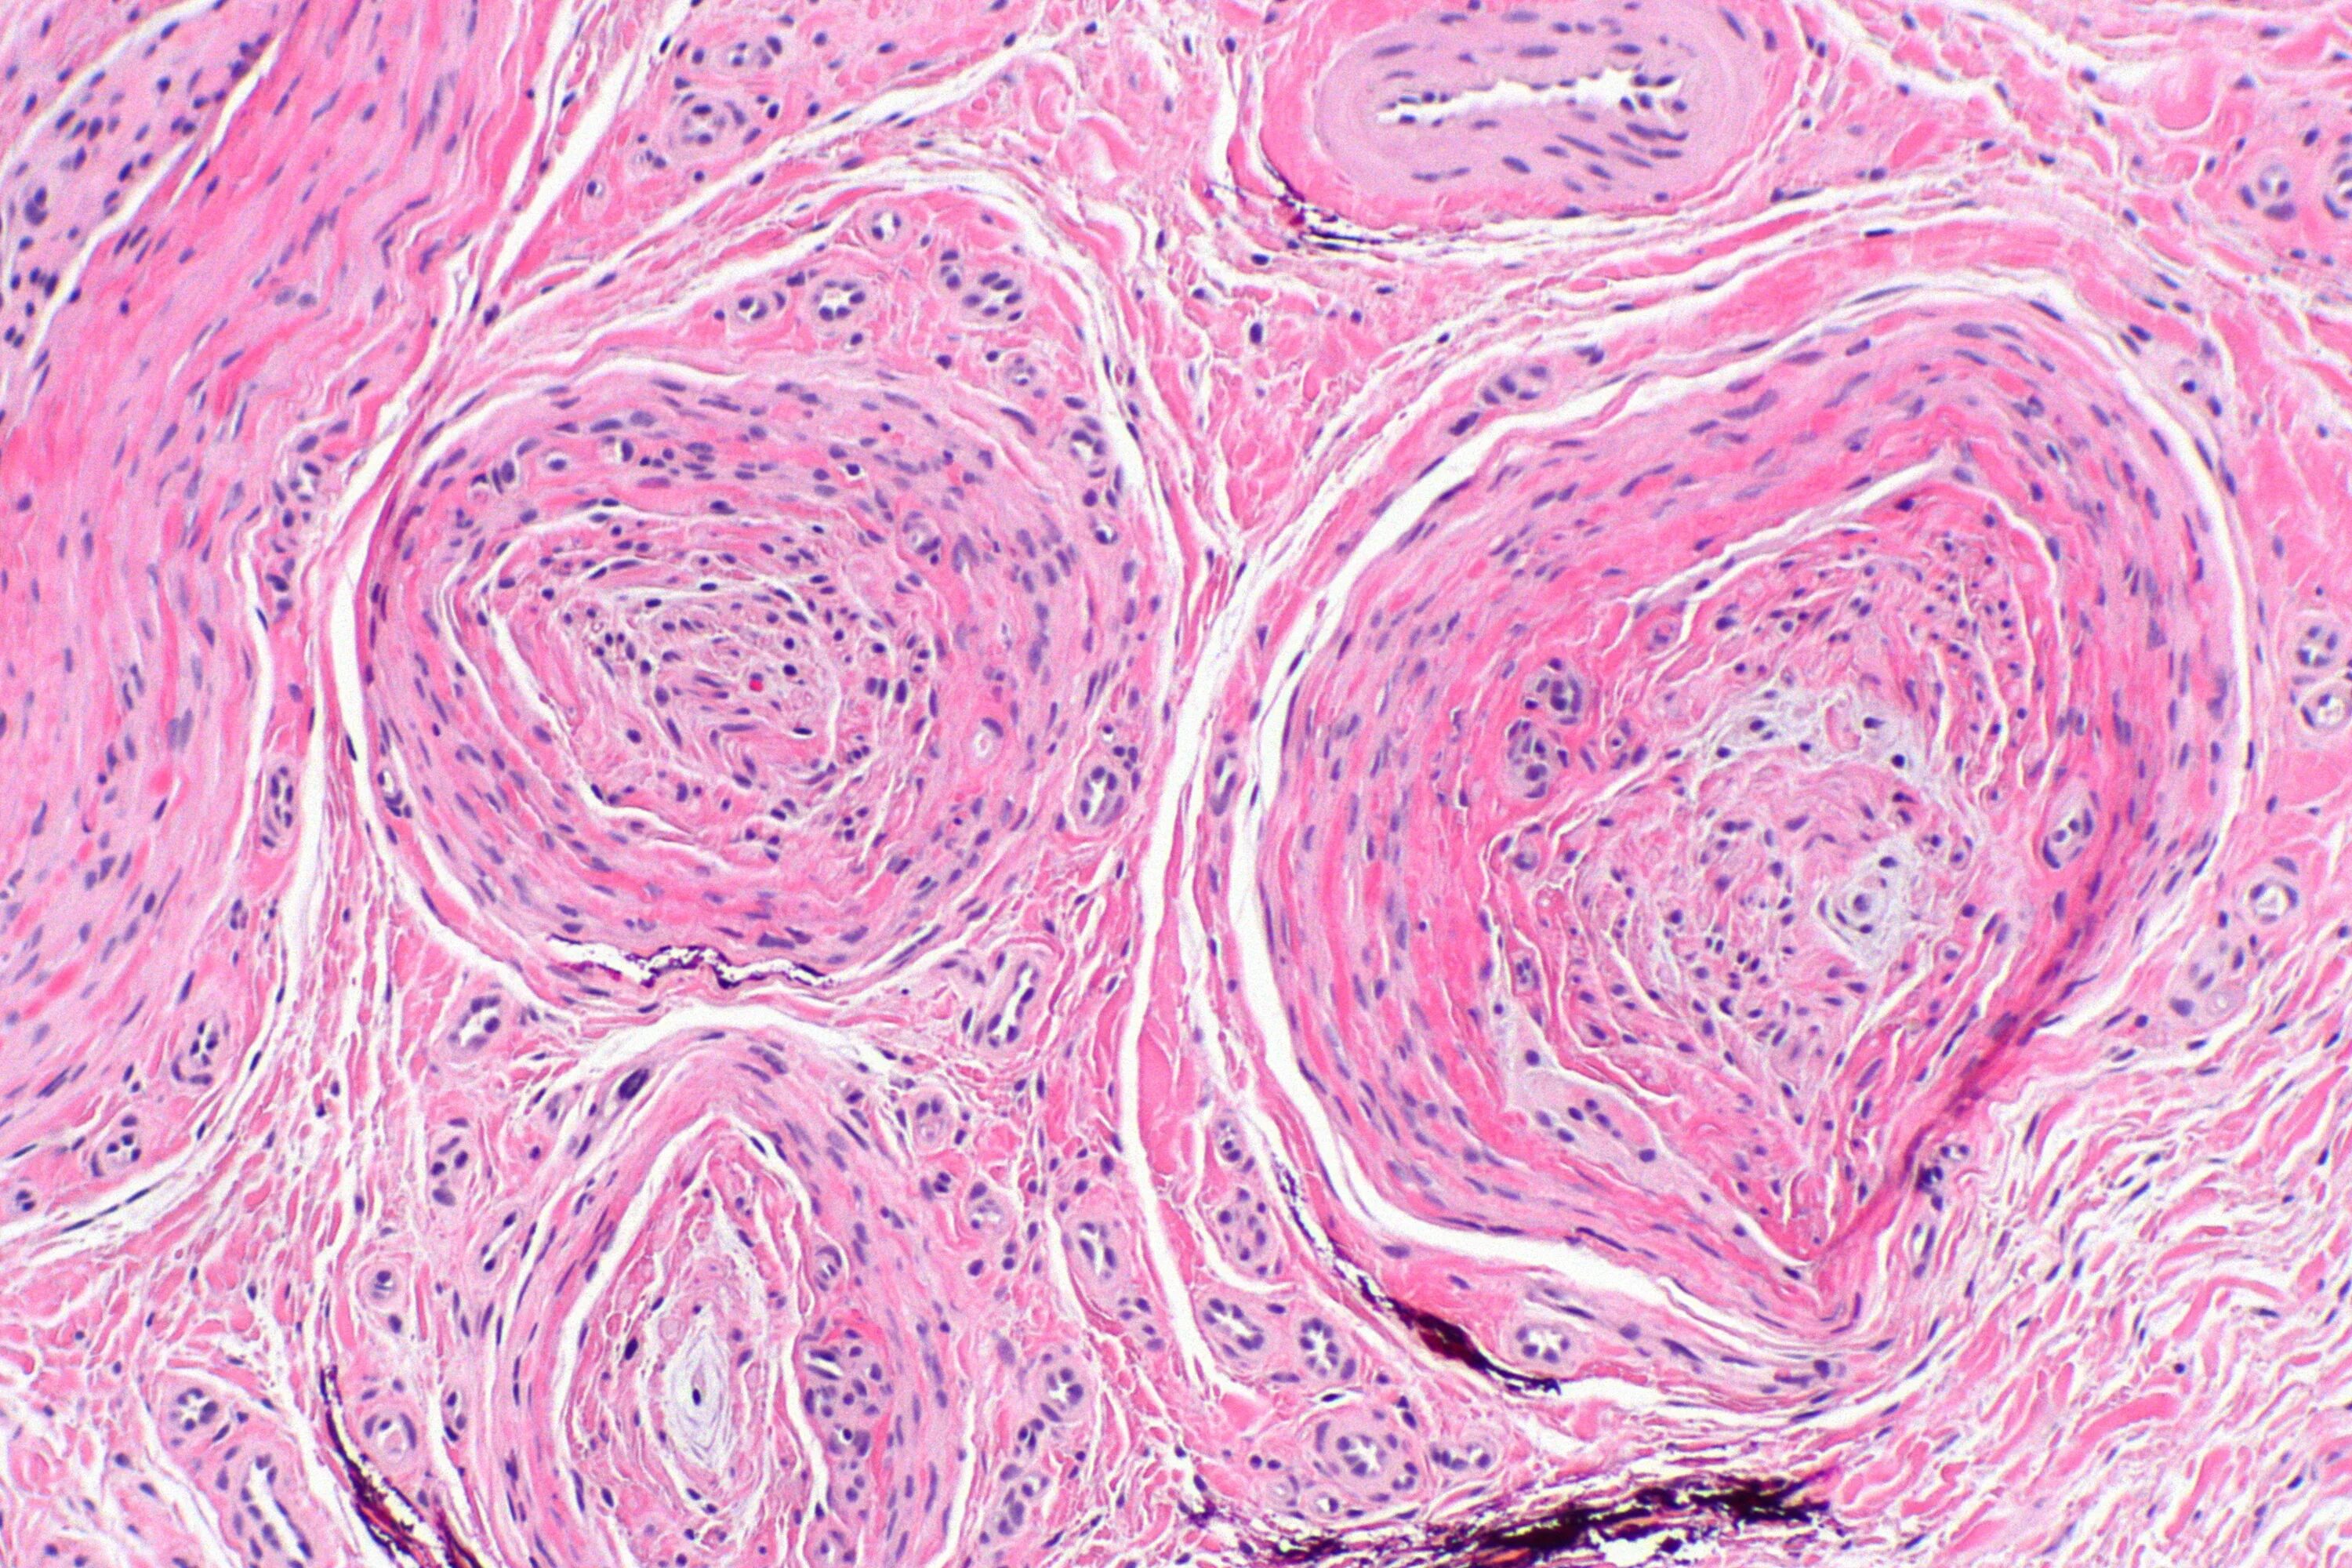

Гистология фиброзные фрагменты